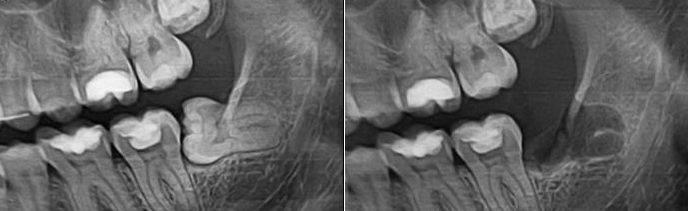

Вырвать зуб: фото до и после

• Проблемы с зубом мудрости.

Если восьмерки неправильно расположены, они не могут нормально прорезаться и доставляют немало проблем. В таком случае остается их удалить.